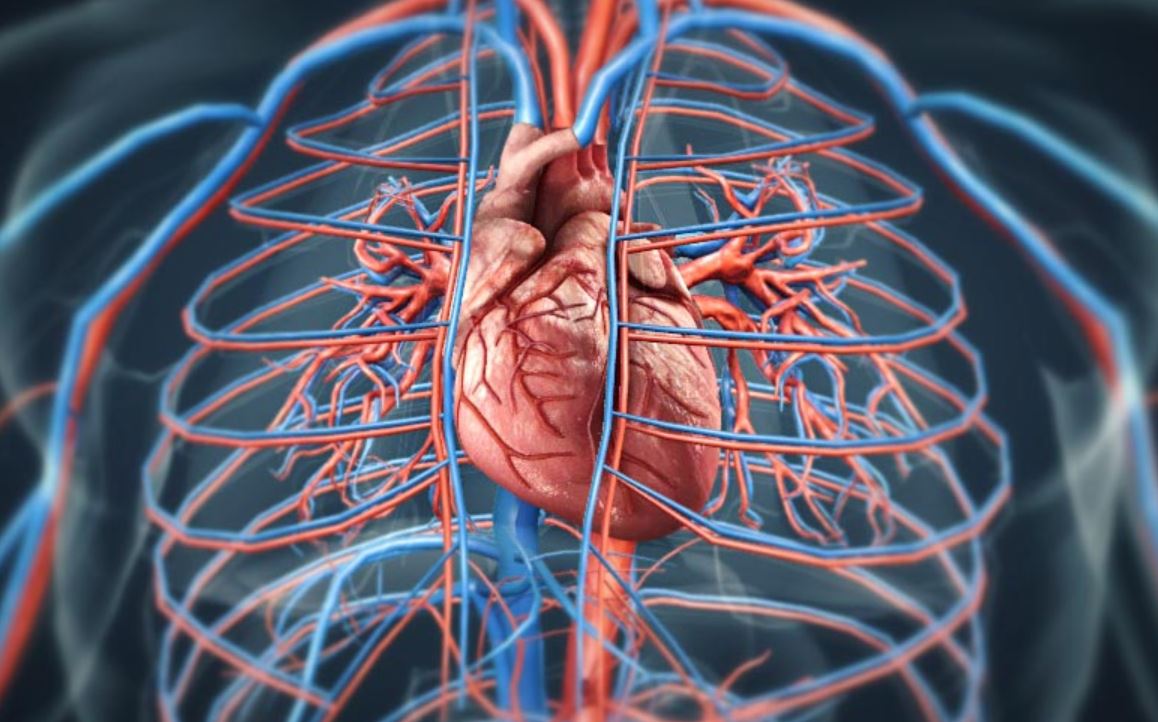

Krvotok koji srce pokreće predstavlja mrežu dugu desetine hiljada kilometara. Kroz arterije, vene i kapilare, krv prenosi kisik, hranjive materije, hormone i druge važne supstance. Bez ovog sistema, nijedna ćelija ne bi mogla opstati. Srce, dakle, nije samo centralni organ, već i ključna karika u održavanju života svake pojedinačne ćelije u tijelu.

U prosjeku, ljudsko srce otkuca oko 100.000 puta dnevno i ispumpa približno 7.000 do 8.000 litara krvi. Kada se to pomnoži s godinama života, dolazimo do fascinantnih brojki koje pokazuju koliko je ovaj organ izdržljiv. Uprkos stalnom radu, srce je osjetljivo na način života. Nezdrava ishrana, stres, nedostatak fizičke aktivnosti i loše navike mogu značajno narušiti njegovo funkcionisanje.